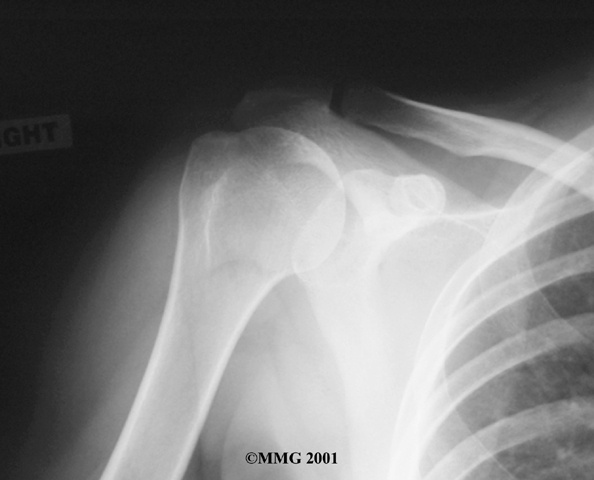

Your doctor may want to take X-rays of the AC joint. X-rays can show narrowing of the joint and bone spurs around the joint, which are signs of degeneration.

X-Rays